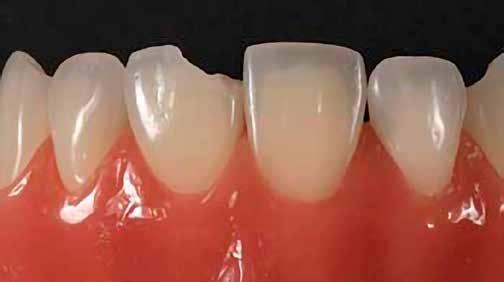

12. ábra: A premoláris fogak preoperatív állapota.

13. ábra: A premoláris fogak postoperatív fotója.